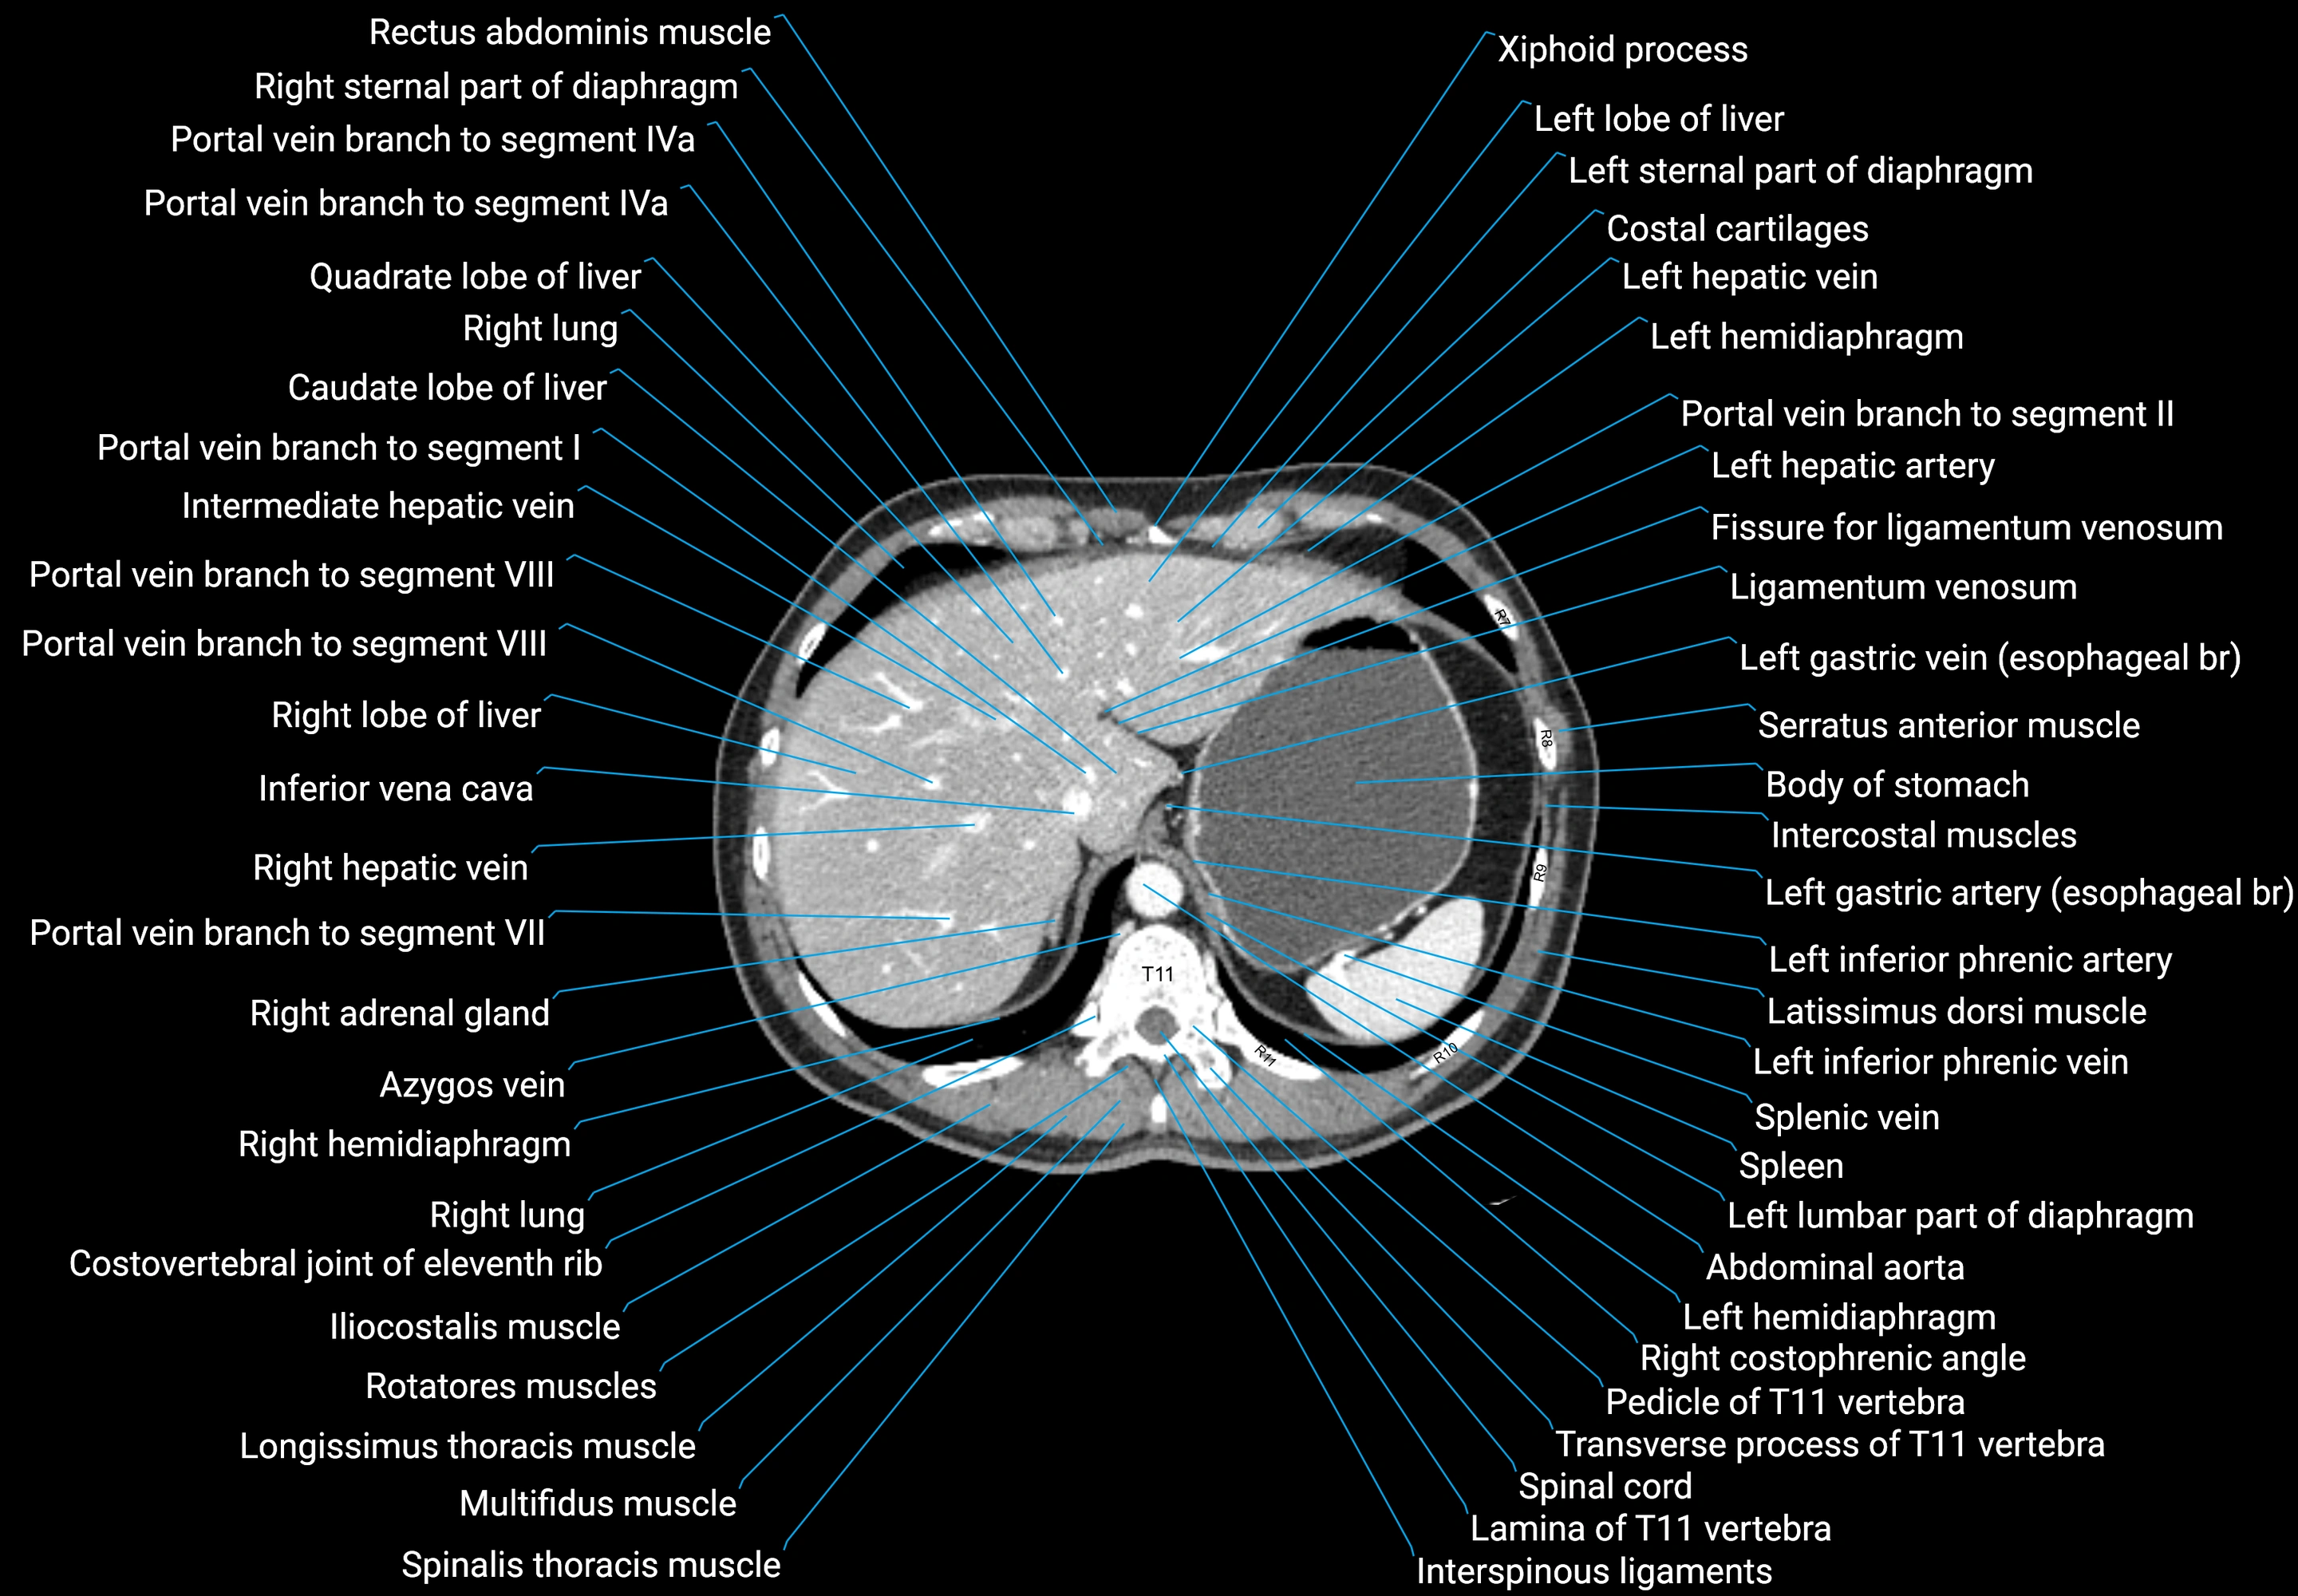

CT images